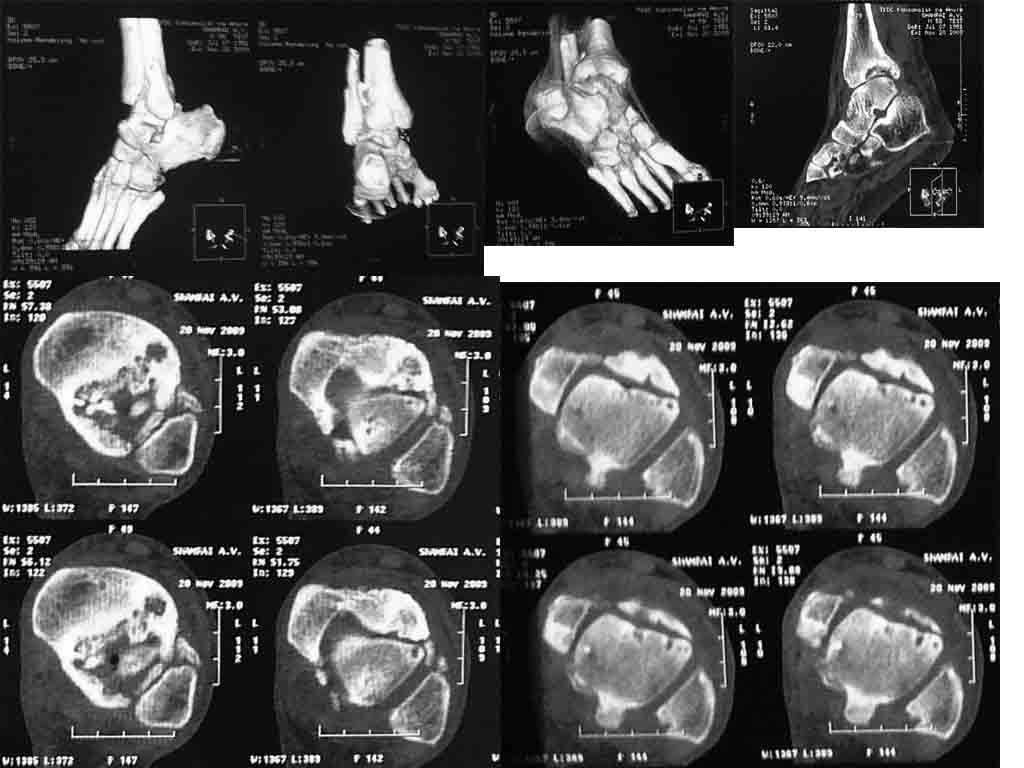

травма 2007 г., лечение консервативно прошу помощи в выборе оперативного пособия. пациент

58 лет, соматически стабилен, платёжеспособен.